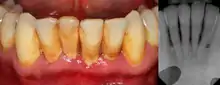

| Gingival enlargement can be a feature in some periodontal diseases. | |

The defining feature of periodontitis is connective tissue attachment loss which may manifest as deepening of periodontal pockets, gingival recession, or both. This loss of support for the teeth is essentially irreversible damage. Chronic periodontitis is generally slow to moderate in terms of disease progression, although short bursts of increased tissue destruction may occur. Ultimately, tooth loss may occur if the condition is not halted. It is termed localized when less than 30% of sites around teeth are involved, and generalised when more than 30% are involved. clinical attachment loss can be used to determine the severity of the condition, where 1–2mm is slight, 3–4mm is moderate and more than 5mm is severe.[5]